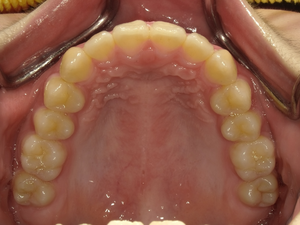

すきっぱ(空隙歯列)CASE5 2023.06.19 10代女性非抜歯〇ご相談内容:上前歯のすきっぱ〇矯正の種類:マウスピース型矯正「インビザラインGO」〇治療期間:14週間〇治療費用:44万円(税込) < すきっぱ(空隙歯列)CASE6すきっぱ(空隙歯列)CASE4 > ブログ記事一覧をみる